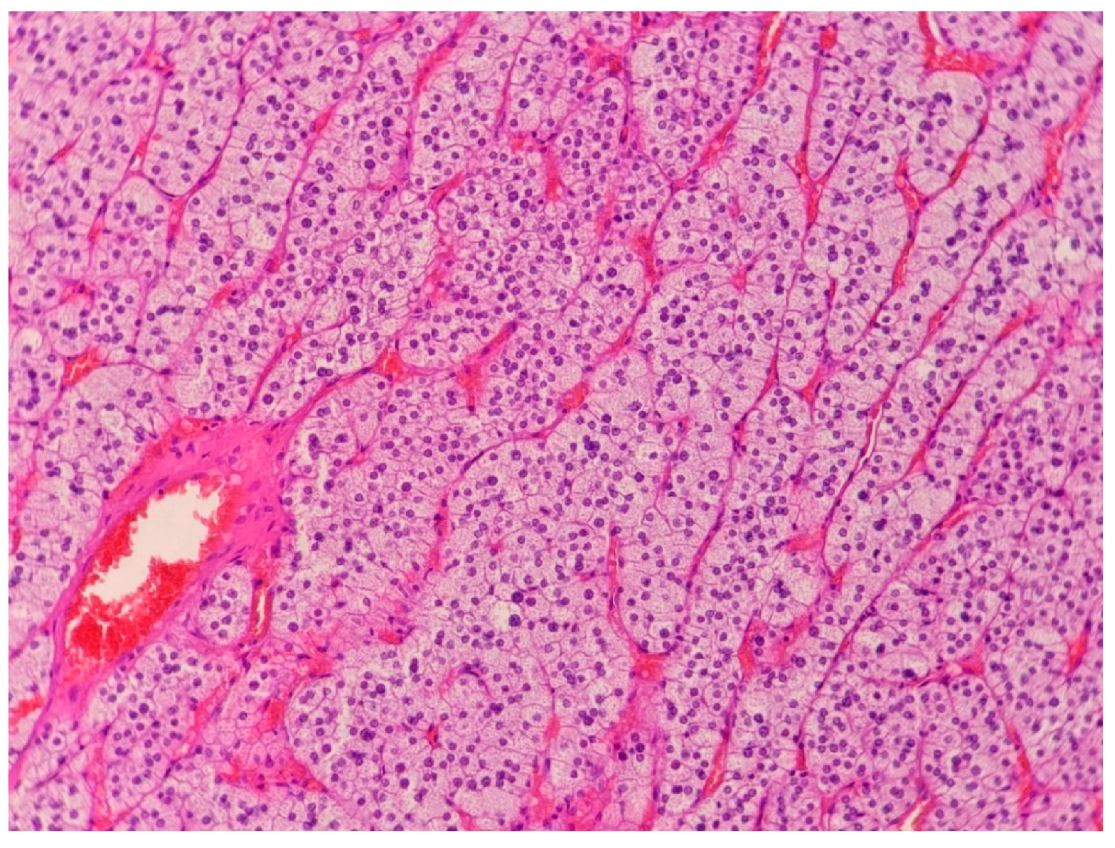

2.2. Case 2